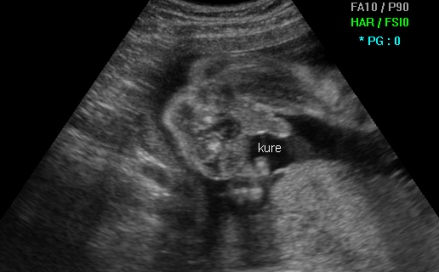

Еве уште едно момченце